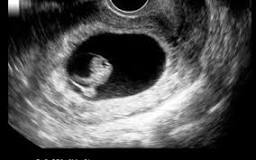

Often, seeing no yolk sac (or a yolk sac that is smaller than normal or otherwise misshapen) at 6 weeks can be a sign of miscarriage. Unfortunately, you'll most likely have to wait until a follow-up ultrasound to be sure.